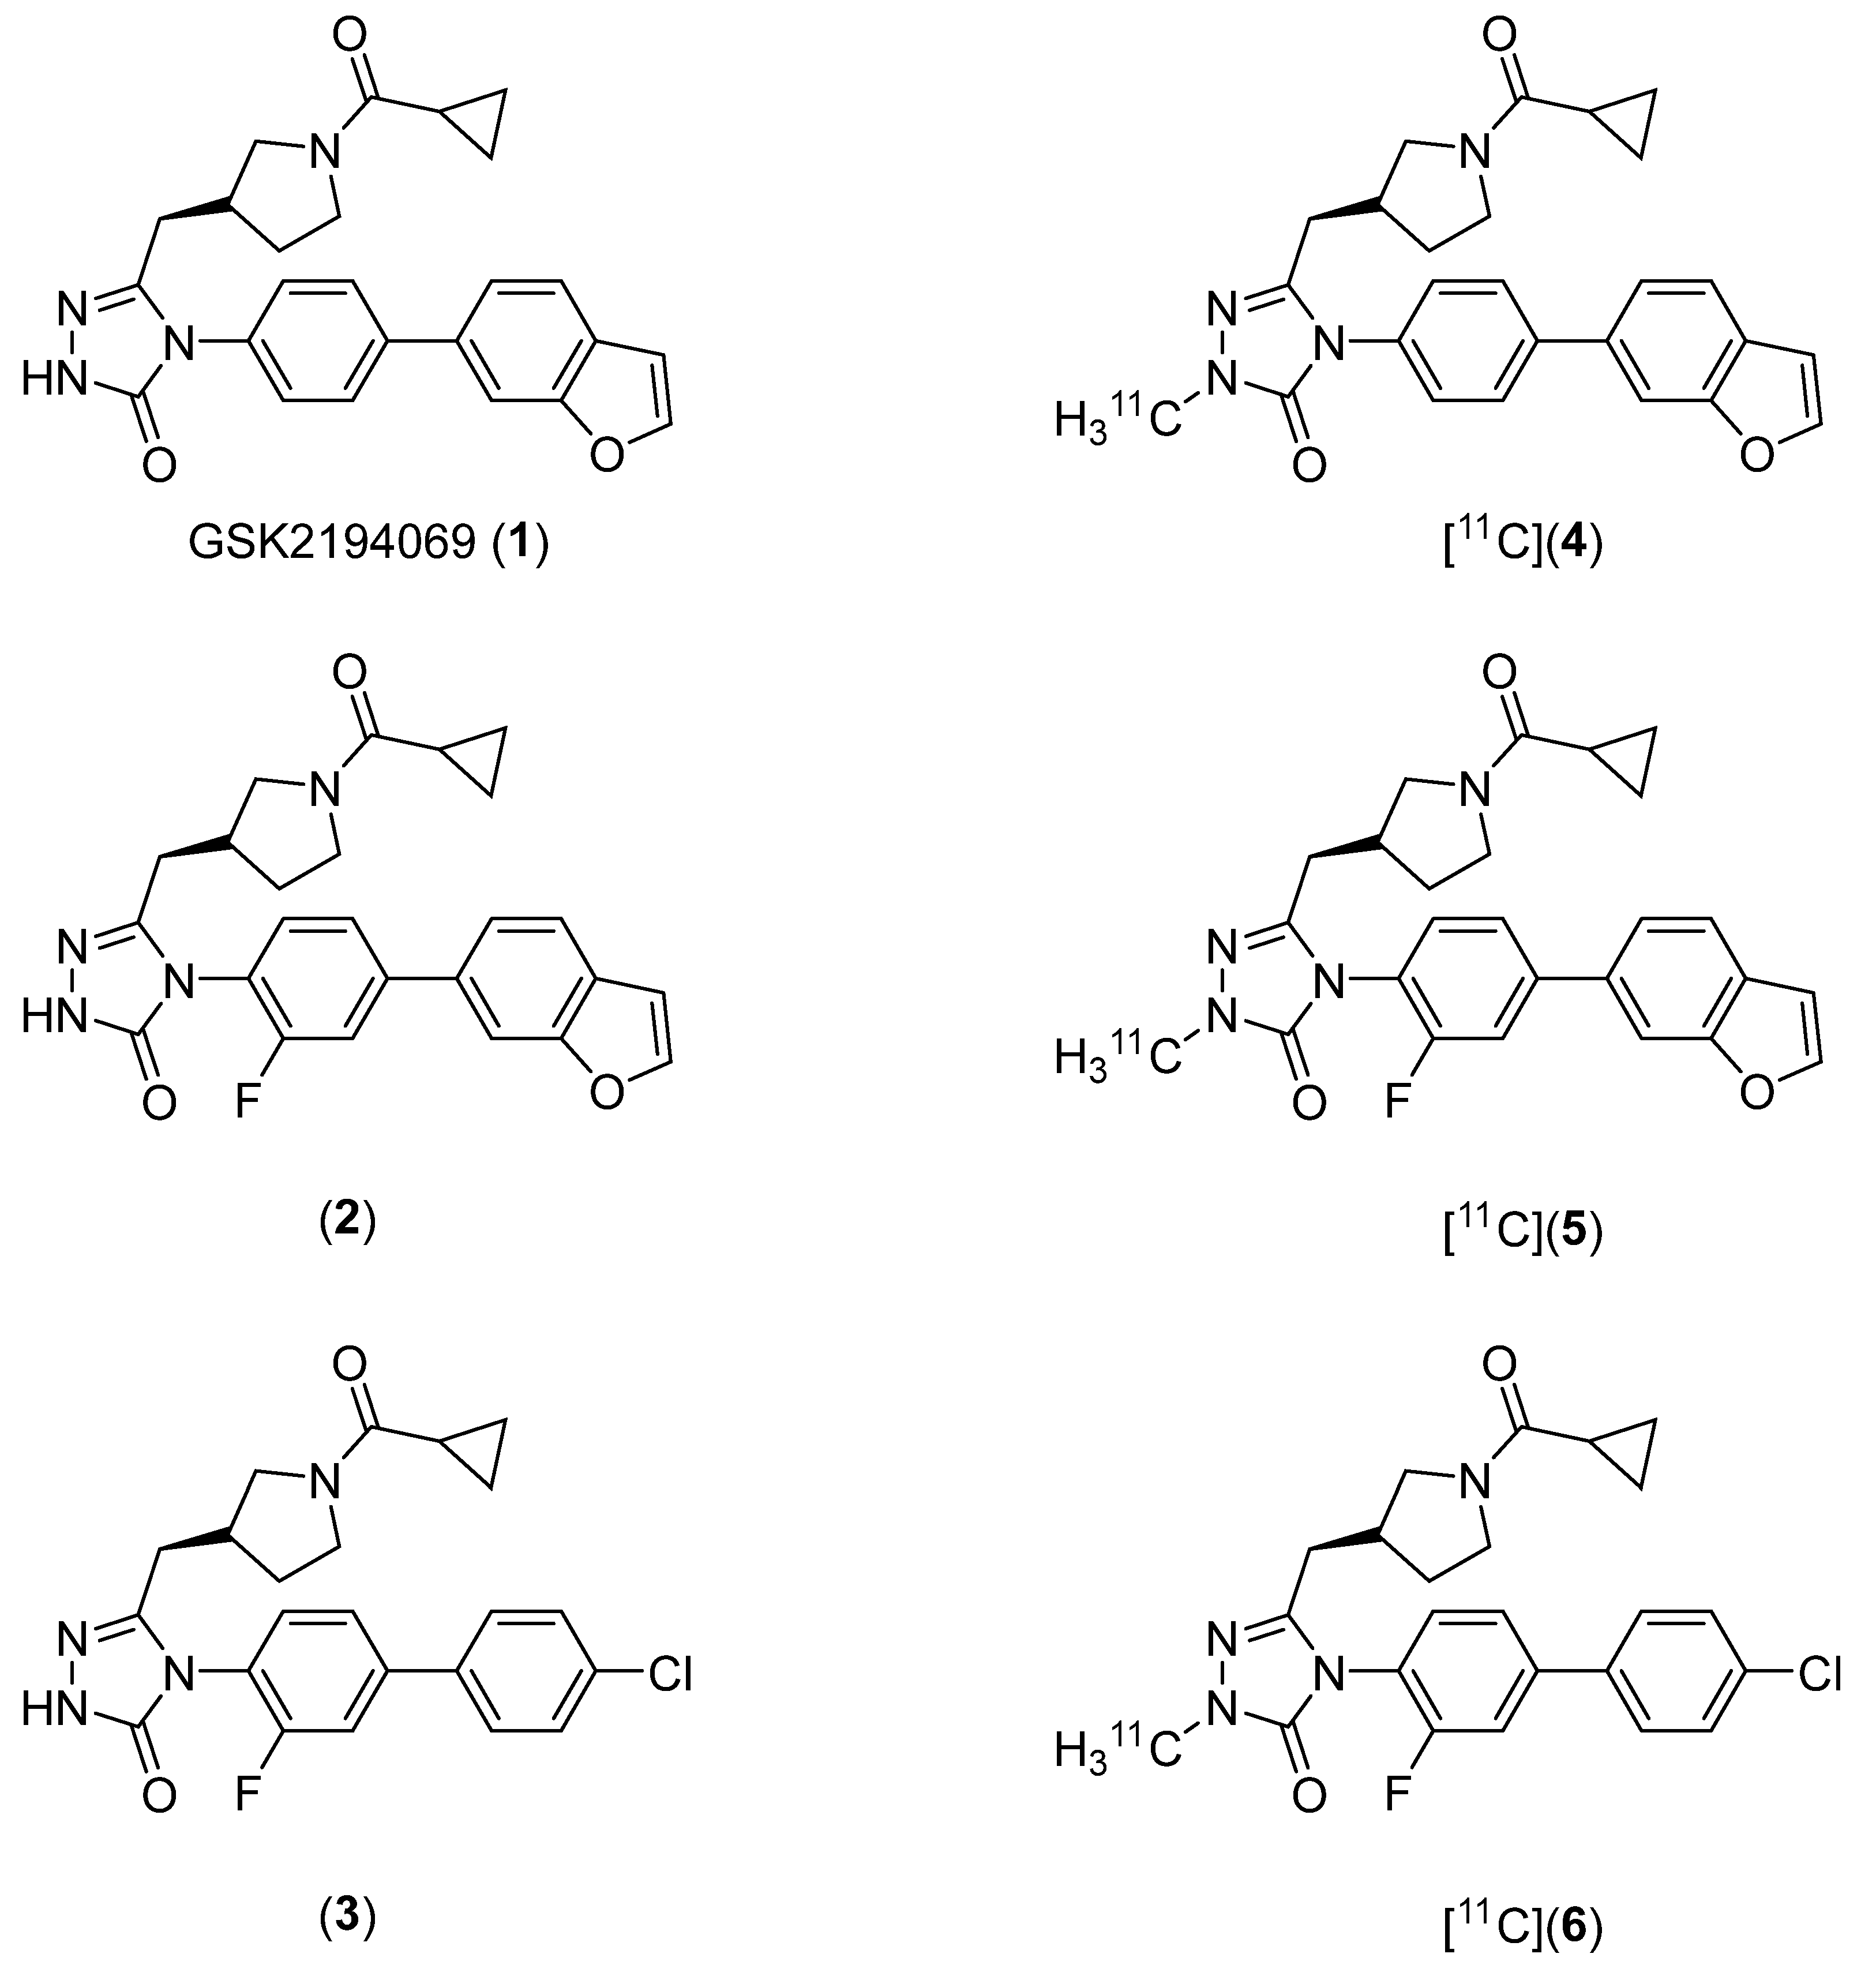

2.1. Lead Compound Identification

2.2. Radiosynthesis